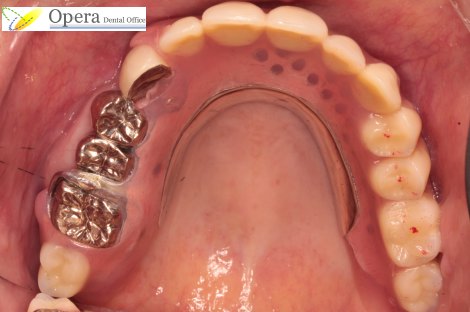

患者さんと相談の結果、自費の義歯ミラクルデンチャーとなりました。

| 費用 | 自費部分義歯ミラクルデンチャー 350,000円 |

| 期間 | 1ヶ月 2回 |

| リスク | ごく稀に金属アレルギーを発症する可能性があります。 咀嚼能力はインプラントに劣ります。 しかし、外科処置をほとんど必要とせず、期間も短く、体に優しく、しかもインプラント1本分の金額で多数歯の治療ができるため、コストパフォーマンス・費用対効果の点で大きなメリットがあると思います。 |

入れ歯のフック(クラスプ)がかかる歯をかぶせものにして連結させればよろよく入れ歯が入ったのですが、綺麗な自前の歯を削るのは忍びなく、全く手をつけずに入れ歯を作ることにしました。